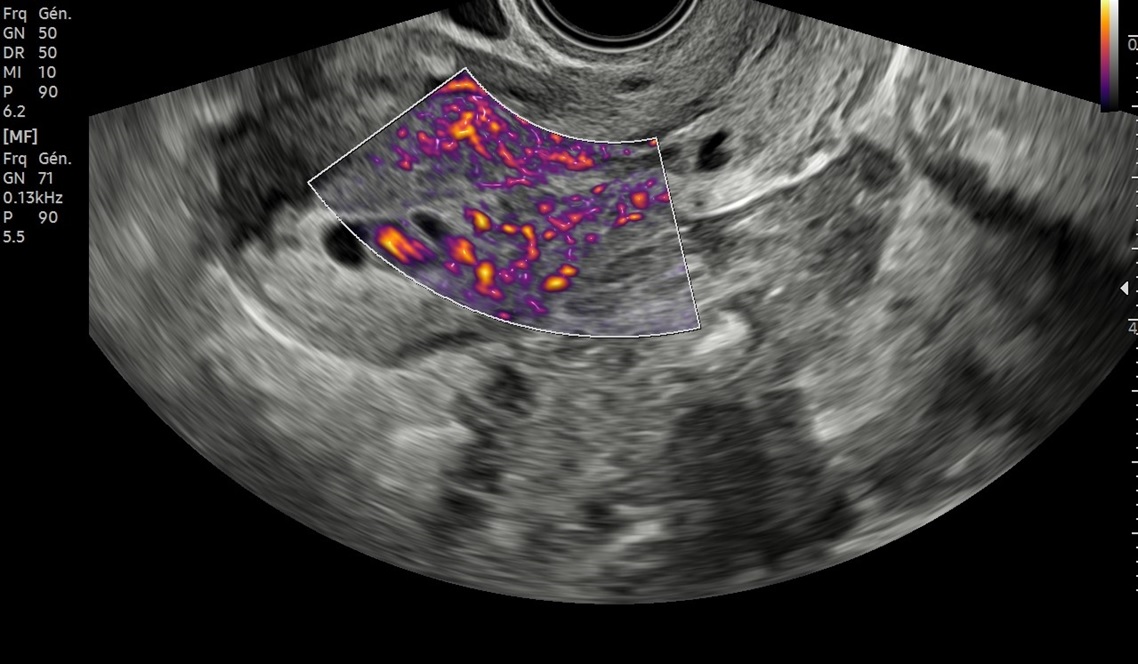

Les sondes de technologie S-Vue™ disposent d'une sensibilité accrue et d'une bande passante plus large que les sondes conventionnelles. Elles garantissent une résolution d’image optimale, même chez les patientes techniquement difficiles. De plus la petite taille et la légèreté de ces sondes améliorent les conditions d'examen au quotidien.

Abdomen, obstétrique, gynécologie

Abdomen, obstétrique, gynécologie, échographie de contraste

Obstétrique, gynécologie, abdomen, pédiatrie

Obstétrique, gynécologie, abdomen